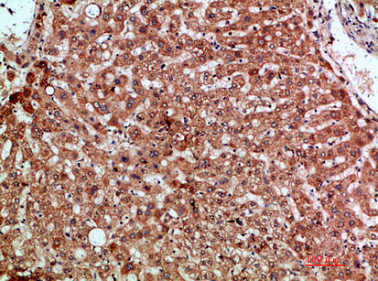

Immunohistochemical analysis of paraffin-embedded human-liver, antibody was diluted at 1:200